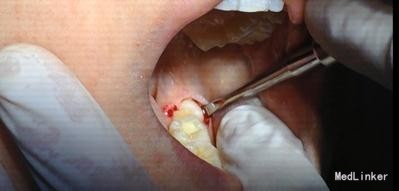

治疗计划:18、28,38拔除。 37重新充填。 48观察。 治疗:28局麻下拔除。 38阻滞下拔除。

拔牙常用牙挺的三步骤、 第一步、楔法:置挺时,插入牙根与牙槽骨之间,然后施力,边旋动,边楔入,使牙在牙槽窝内逐渐松动 ↓ 第二步、推法:将挺刃插在所拔牙牙齿的近中面或颊侧面与牙槽骨之间,使挺刃的凹面朝向根面凸面支靠在颊侧近中牙槽嵴上作为支点。用靠近冠部的挺刃推动所拔牙,使该牙受力后被推向远中或者舌侧而松动,但不包含使牙脱出牙槽的力。 其实说白了推法楔法差不多,只是用力方向幅度大小不同。 楔是向下楔入,推是增大间隙。 第三步、挺法:置放方法与推法一致,只是用力方向变了。向远中面方向旋动牙挺时,使紧贴颈部根面的挺刃向所患牙使力,使其受力后被挺向远中并向合面方向移动。再逐渐加大牙挺旋动的幅度,并将挺刃逐渐向牙槽内插入(配合楔法),牙的松动度也随之增大。最后,使该牙将向合面与远中的合力方向松动脱位。